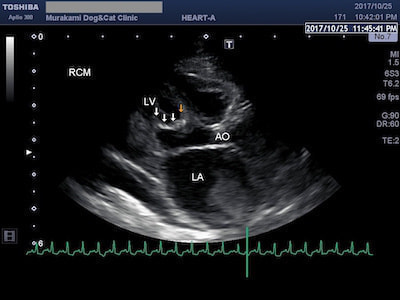

拘束型心筋症(RCM)

肥大型心筋症(HCM)と並んで、猫によくみられる心筋症の一つが拘束型心筋症(RCM)です。HCMと違って心筋の肥大は認められませんが、心内膜の線維化や、心室内に過剰な線維性構造物(過剰調節帯)が認められ、心臓の動きが悪くなる(拘束される)のが特徴です。

RCMに伴う胸水と左房内血栓

RCMでは心室の動きが拘束されることにより拡張機能が妨げられ、僧帽弁逆流や三尖弁逆流が生じた結果、左房拡大や右房拡大が顕著に認められます。拡張した心房内では血流の鬱滞や乱流が生じるため、肺水腫や胸水の貯留、血栓が生じやすくなります。治療には血管拡張薬や利尿剤、血栓予防薬を用います。